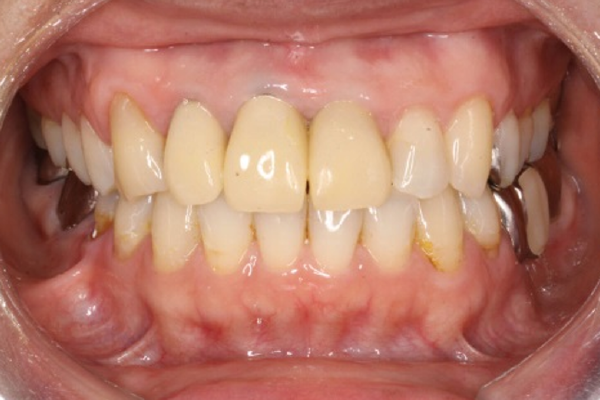

受け口の治療前

上の写真のように、以前であれば外科矯正を行ったようなケースでも、今はインプラント矯正によって、受け口(下顎前突)や、オトガイ部の突出感も改善できることがあります。

①受け口(下顎前突)の矯正治療例(50代女性・治療期間2年2か月)

| 年齢・性別 | 50代女性 |

| 治療期間 | 2年2か月 |

| 抜歯 | なし |

| 治療費 | 100万円(調整費、保定費まで含む総額制) |

| 備考 | 裏側矯正、QH拡大、歯冠長延長術、補綴物再作製 |

| リスク・副作用 | 痛み・治療後の後戻り・歯根吸収・歯髄壊死・歯肉退縮 |